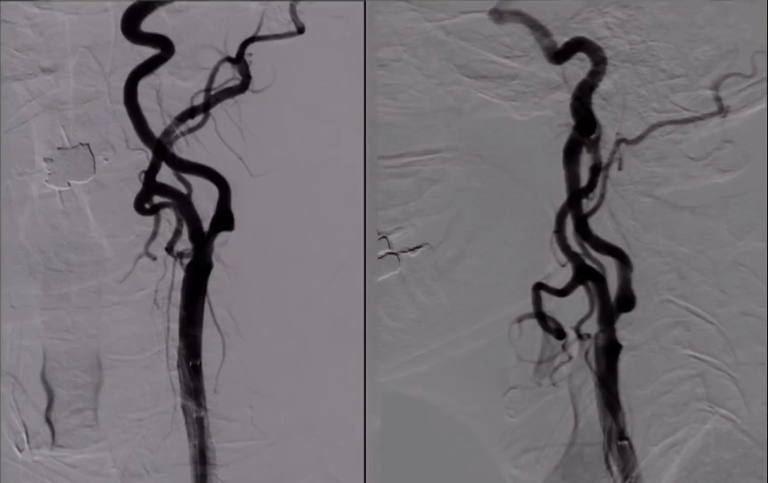

DSA:双侧颈内动脉起始部重度狭窄;前交通及双侧后交通未开放。

8F Fluxcap®球囊导引导管在5FMPA多功能125cm导管同轴辅助下送至右侧颈总动脉,微导丝送至C4段,沿微导丝送入6mm保护伞至C2段平直段,手推造影显示保护伞打开良好。

沿保护伞导丝送入4.0mm×30mm球囊,充盈球囊导引导管的球囊阻断血流,于狭窄段定位后命名压扩张球囊,泄球囊时在球囊导引导管的体外端予以负压回抽血液,取出一2mm血栓。经Fluxcap®球囊导引导管输送7.0-10.0mm×40mm自膨支架(Protégé RX)至狭窄段确认位置后释放。应用125cm多功能导管回收保护伞,多功能导管体外端予以负压回抽血液,保护伞内有血栓。

造影可见残余狭窄10%左右,颅内各分支血管通畅。